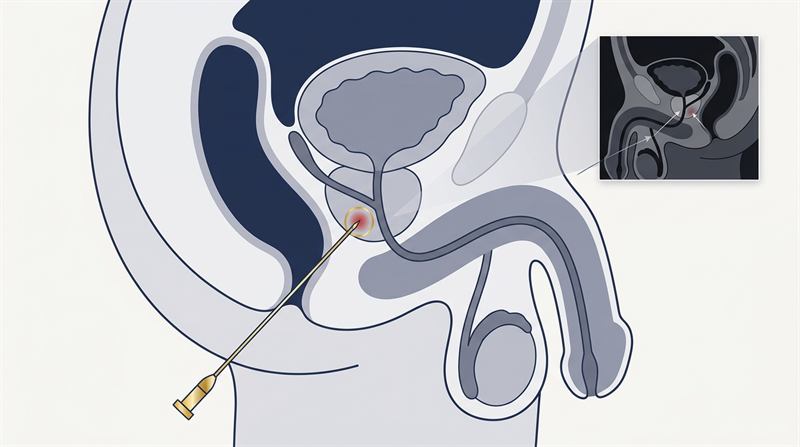

Transperineal Prostate Biopsy - MRI Fusion for Prostate Cancer

Dr Raji Kooner explains transperineal biopsies and their application in diagnosing prostate cancer.

MRI-Guided Transperineal Biopsy

Dr Kooner is one of the first in Australia to perform transperineal ultrasound-fusion guided biopsy into the prostate. This technology allows more accurate biopsy with fusion of MRI abnormalities onto ultrasounds used in theatre. This then allows the abnormalities to be targeted more accurately7.